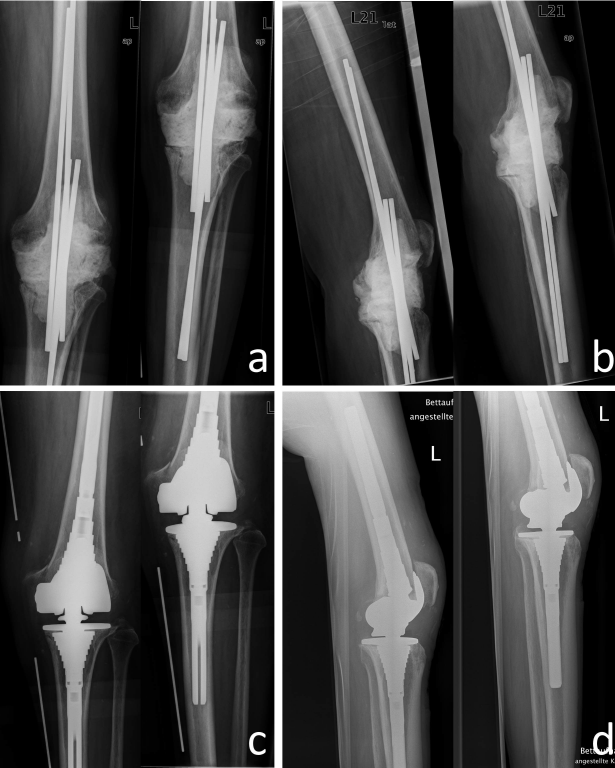

Surgical debridement and artificial joint explantation were carried out in all cases with temporary implantation of antibiotic containing cement spacer. In 85.7% (30) of the cases we used mobile spacers; in 14.3% (5) we introduced fixed spacers with intramedullary fixation (Figure 1 [Fig. 1] and Figure 2 [Fig. 2]). In those cases with mobile spacers we used the spacers produced by AGC Style Company Biomet Orthopedics Inc. Warsaw, USA. The system consists of a femoral shape size of 60 to 75 mm in 5 mm increments and a tibial mold size of 65 to 80 mm also available in 5 mm increments. Both are each filled with 80 g of cement and adapted to the local anatomy (Figure 1 [Fig. 1]). As intramedullary/fixed placeholder carbon or metal rods were intramedullary introduced and covered and surrounded with cement according to the defect size in the knee. In those cases we used Copal G+C Heraeus Medical GmbH (Wehrheim, Germany), each with 1 g of gentamicin and clindamycin applied to 40 g cement.

Figure 2: 79-year-old patient with TKA infection left. a) Radiograph of the knee anterior-posterior and b) lateral after temporary arthrodesis with intramedullary fixation with titanium rods and cement mantle. c) X-ray knee anterior-posterior and d) lateral after re-implantation of a revision-TKR (Typ S-ROM, Company DePuy Synthes, West Chester, PA, U.S.A.)